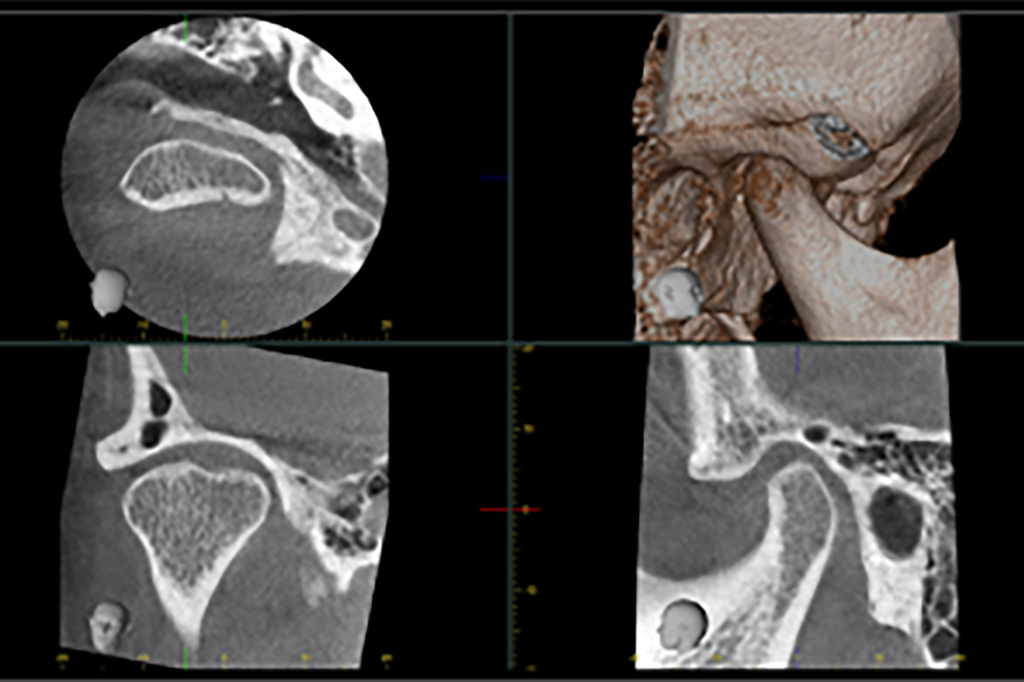

• ■顎関節検査

兵庫県南あわじ市・医療法人 太田歯科・矯正歯科

当院では義歯作製の一環として、顔貌検査、顎関節検査、顎運動検査、咀嚼機能検査等を取り入れています。

総合診断

(顔貌・CT)

- - 8,000円